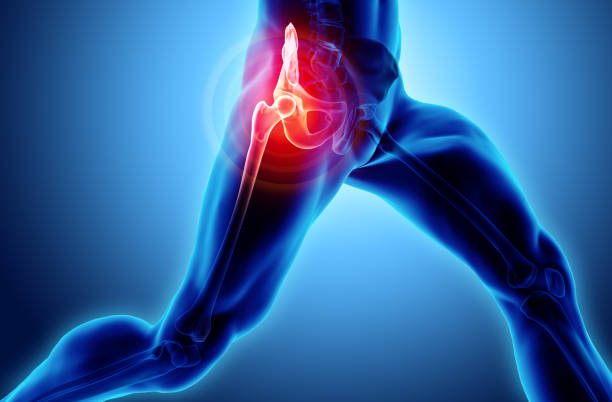

골반통증은 많은 사람들이 겪는 건강 문제 중 하나입니다. 장시간 앉아있거나 일을 많이 하다보면 골반 주변 근육이 약해지고 불균형해지는 경우가 많아 골반통증이 발생할 수 있습니다.

이런 골반통증의 경우 근육이 약해지거나 자세불량 등 다양한 이유가 있는데요.